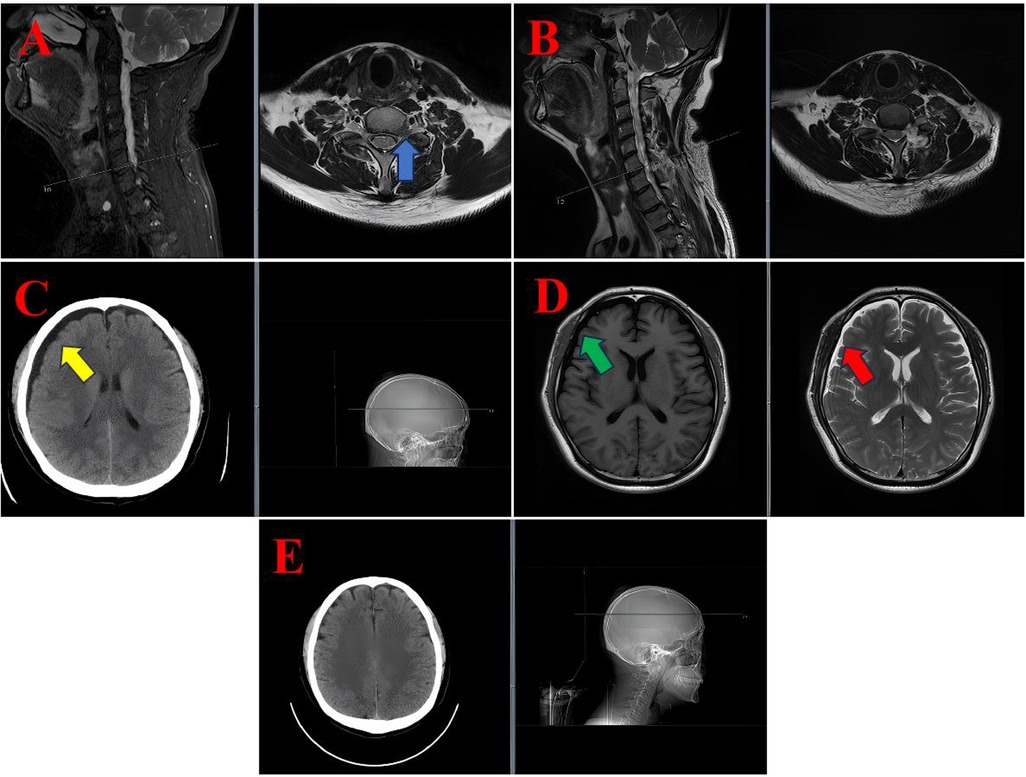

Background: Biportal Endoscopic Spinal Surgery (BESS) is a minimally invasive technique that has gained popularity for performing spinal procedures, including discectomy, decompression, and interbody fusion, in the cervical, thoracic, and lumbar regions. Whilst dural tears, epidural haematoma and transient paresthesia are well-documented complications associated with BESS, cases of subdural hygroma remain exceedingly rare. The present study presents a case series of three patients who developed postoperative subdural hygroma following BESS. An accompanying literature review was conducted in order to explore potential mechanisms and management strategies. Case Presentation:The initial case pertained to a 35-year-old male patient who underwent a cervical discectomy and foraminal decompression via BESS for the treatment of cervical spondylosis. Subsequently, the patient developed a cranial subdural hygroma. The second patient, a 53-year-old male, underwent a lumbar discectomy and decompression via BESS for lumbar disc herniation with concomitant spinal stenosis. Postoperative imaging revealed extensive lumbar subdural hygroma. The third case report concerns a 74-year-old male patient who underwent BESS decompression surgery for lumbar spinal stenosis. Postoperatively, the patient developed a subdural hygroma in the lower lumbar region. Conclusion: The development of subdural hygroma following BESS may be attributed to a combination of factors, including occult dural tears, abrupt alterations in intraspinal pressure, and ischemia-reperfusion injury. In view of the potential clinical implications of this rare complication, greater awareness and monitoring is warranted in the postoperative management of patients undergoing BESS.